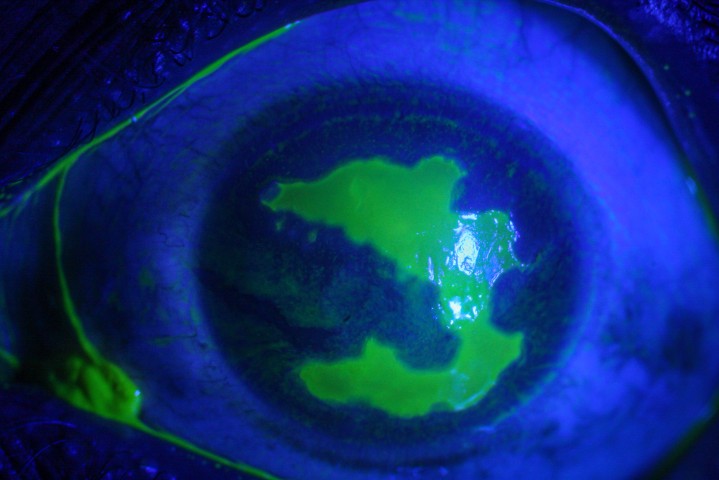

The following day, VA had improved to 6/24, and IOP was normal. Fig 2 shows inferior displacement of the submacular haemorrhage away from the fovea. The patient was instructed to continue face-down posturing for another two days. The patient subsequently continued monthly intravitreal bevacizumab injections, then moved to a treat-and-extend regimen.

Fig 2. Presence of gas bubble and

displaced subretinal blood